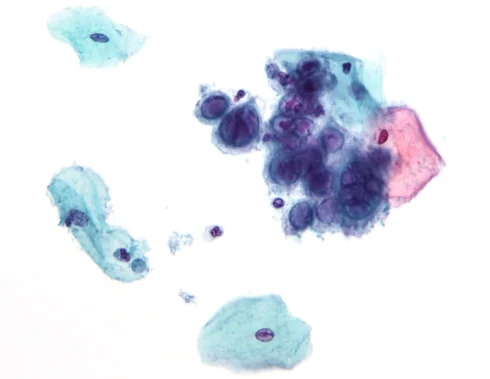

اثر سیتوپاتیک: انواع اثرات سیتوپاتیک در تشخیص

اثر سیتوپاتیک چیست؟ هنگامی که ویروس به سلول میزبان حمله کند، ساختار آن تغییر میکند.[بیشتر بخوانید]